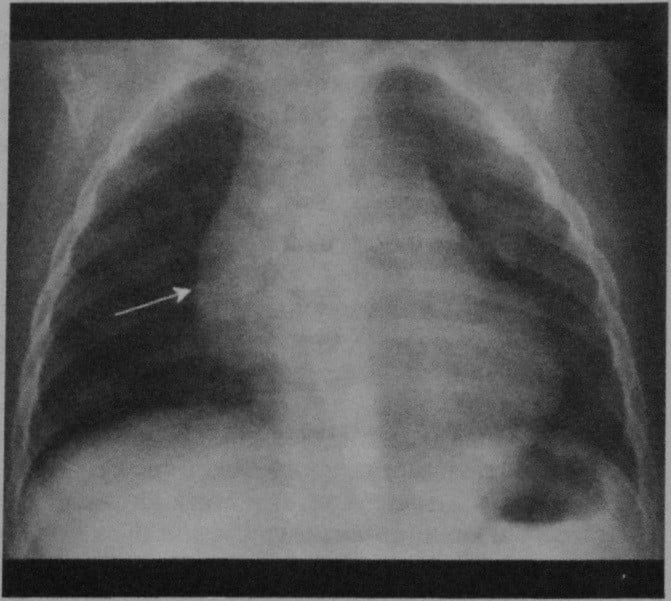

Тимомегалия: что это такое и как проявляется